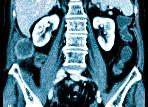

Основное преимущество этого способа изучения состояния здоровья внутренних органов заключается в том, что в процессе сканирования организма, компьютерный томограф передает на экран монитора трехмерное цифровое изображение, которое в полной мере отображает возможное наличие патологических состояний, либо их отсутствие.

Этот вид лучевой и компьютерной диагностики применяется для послойного обследования строения органов брюшной полости, определения имеющейся в них патологии. Для обследования используется рентгеновское излучение, даваемое томографом и позволяющее получать послойные срезы тканей. Регистрация данных происходит специальными датчиками, передающими сигнал на компьютер, снабженный специальным пакетом программ обработки сигналов и выведения результата на монитор с фиксацией на носителе информации.

Во время процедуры станина стола движется относительно аркообразного сканнера, содержащего датчики,  фиксирующие данные в виде моментальных снимков и видео-картинки и передающих их на компьютер. Полученные «срезы» обрабатываются при помощи программ и визуализируются на экране монитора. Одновременно их записывают на устройство хранения информации.

Компьютерная томография брюшной полости – один из самых современных методов обследования, позволяющий при помощи рентгеновских лучей получить точные снимки с контролируемой величиной среза и плоскости. В ходе диагностики врач получает трехмерную картинку, на которой можно увидеть малейшие патологические изменения, невидимые при других методах, таких, как УЗИ.